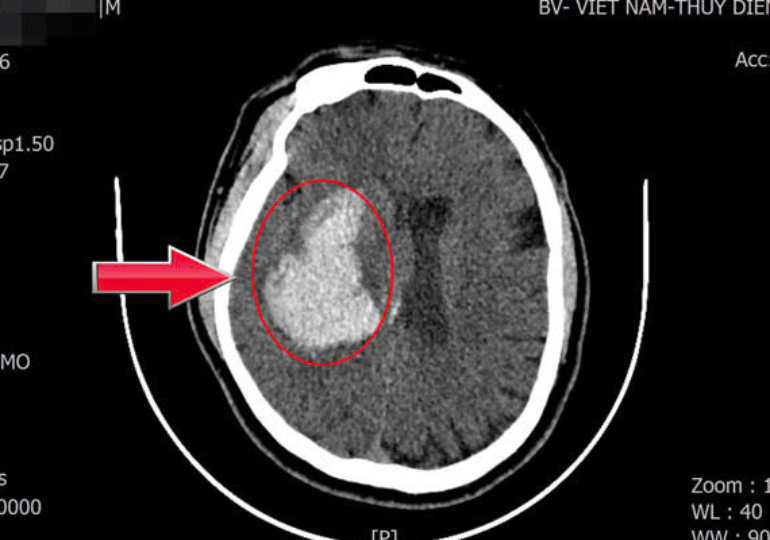

Tăng huyết áp không triệu chứng, người đàn ông 44 tuổi đột ngột ngã gục

17/02/2026 05:00

Người đàn ông 44 tuổi ở Quảng Ninh đột ngột đổ gục vì xuất huyết não. Khi cấp cứu, huyết áp của bệnh nhân đã ở mức nguy kịch, đe dọa trực tiếp tính mạng.